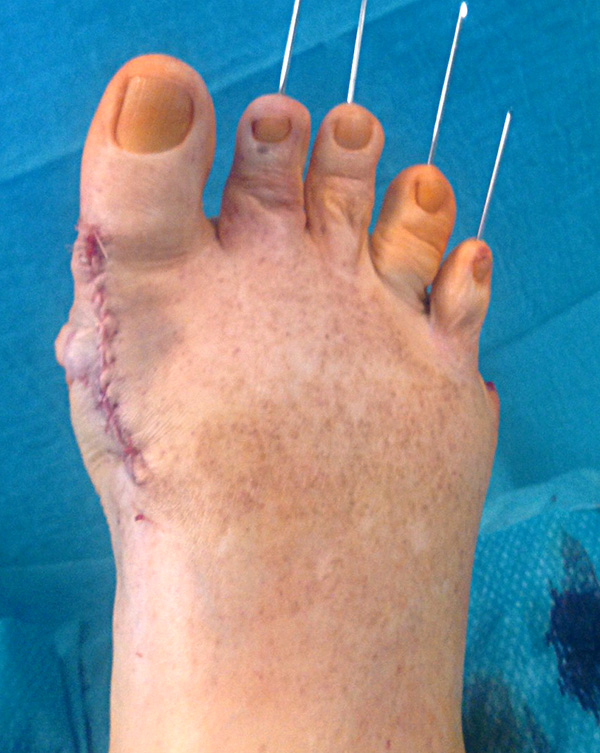

Die Raffung des plantaren Kapselgewebes erfolgt mit 0er Vicryl. Besteht eine Lateraldeviation der Kleinzehen kann diese durch eine tibialseitige Raffung korrigiert werden. Tillmann beschreib in diesem Zusammenhang die Raffung der plantaren Gelenkkapsel tibialalseitig mit Einstich an der Grundgliedbasis und auf Höhe der metatarsalen Resektionsebene.

Das MTP V wird mittig gerafft zur Verhinderung eines Digitus quintus varus.

Das plantare Fettpolster wird in die Auftrittsfläche reponiert und mit Vicryl vernäht. Die plantare Hautnaht erfolgt mit robustem, nicht resorbierbarem Nahtmaterial (z.B. Ethilon 2,0).

Abschließend erfolgt die temporäre K-Daht Fixation sämtlicher Kleinzehen in achsgerechter Stellung. Die Strecksehnen werden in Verlängerung vernäht.

Mobilisation des Patienten im flachen Verband-Schuh für 4-6 Wochen. Die Dauer richtet sich nach der Therapie im Bereich des ersten Strahls.

Der Fadenzug erfolgt plantar nach 21 Tagen. Fäden am Fußrücken können nach 14 Tagen entfernt werden.

Die Entfernung der K-Drähte wird sechs Wochen postoperativ im Rahmen der Sprechstunde geplant. Anschließend empfiehlt sich eine weitere Redression der Kleinzehen bis 3 Monate postoperativ bis sich das Narbengewebe ausreichend stabilisiert hat.